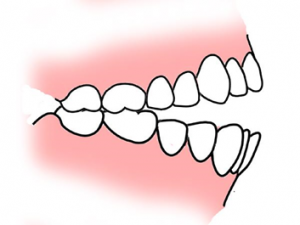

①上顎前突

上顎前突とは上の前歯や上あごが下の歯よりも前方にでていることをいいます。

大きく二つに分類すると上の歯の傾斜によって前に出ている歯自体のものと、下の歯に比べて上の歯全体が大きく、上の歯茎と歯が前方にでている骨格的なものに分かれます。

上の歯の傾斜によって前歯が出ている場合の原因は様々ですが、幼少期の指しゃぶりや舌で上の前歯を押す癖によって起こりやすいと言われています。

また鼻呼吸ではなく口呼吸をしている場合も歯が前に出てきてしまいます。

口呼吸になるとお口の中が乾燥しやすくなり、歯周病や虫歯のリスクが高くなるだけではなく、口臭の原因にもなります。

治療していく方法は様々ですが、表側矯正・裏側矯正・インビザラインなどで歯を正しい位置に移動させるのが一般的です。

上顎前突は日本人で2番目に多い不正咬合となっています。